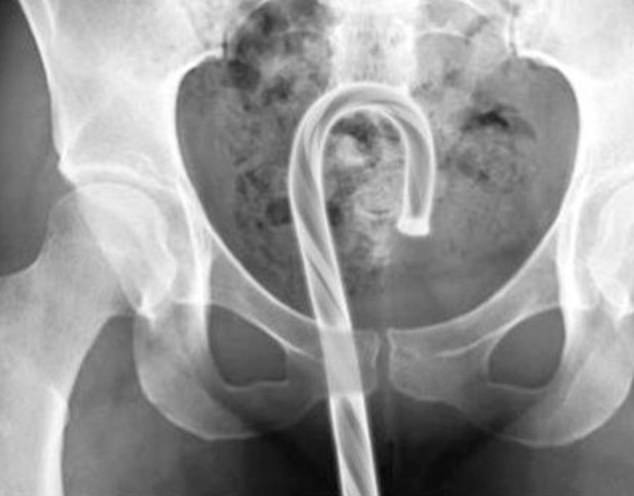

It was found that the rectum is the most common place for bizarre items to get stuck. Some of the objects include household items such as aerosol can, plastic pill bottle, beer bottle, and a plastic cigar holder.

- ‘Has vibrator in rectum and tried to remove it with screwdriver and lacerated rectum; object in colon now.’